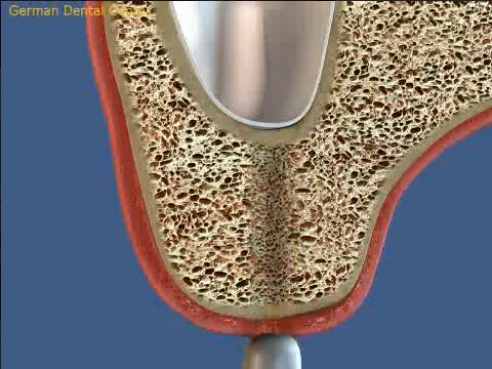

- Имплантация